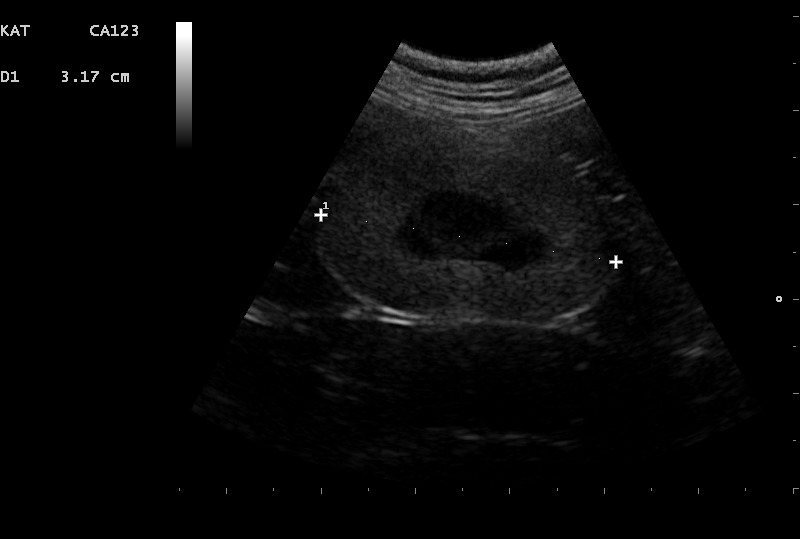

Bij chronisch nierfalen verliezen de nieren met verloop van tijd hun functie. De oorzaak is helaas vaak lastig te achterhalen maar er kan bijv. sprake zijn van een aangeboren afwijking, infectie of uitdroging. Door middel van een echo van de urinewegen kan meer informatie worden verkregen over een mogelijke oorzaak.